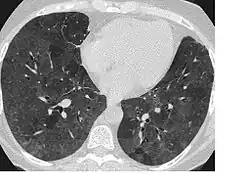

La radiographie pulmonaire, peut montrer une pneumopathie interstitielle diffuse d’aspect micronodulaire (parfois avec des opacités dépolies dans la partie inférieure et moyenne du poumon). Les résultats sont normaux chez environ 10 % des patients. Au scanner, on retrouve des opacités localisées ou diffuse. Les épreuves fonctionnelles respiratoires montre une réduction de la diffusion du monoxyde de carbone (DLCO). Beaucoup de patients ont une hypoxémie de repos, et tous les patients présentent une désaturation à l’exercice physique[3].

Les patients présentant une PHS subaiguë développent progressivement une toux, une dyspnée, une fatigue, une anorexie, une perte de poids et une pleurésie. Les symptômes sont semblables à ceux de la forme aiguë de la maladie, mais moins sévères et durent plus longtemps. Les radiographies pulmonaires, montrent des opacités micronodulaire ou réticulo-nodulaires prédominant le plus souvent dans les zones moyennes et inférieures du poumon[3]. Ces symptômes peuvent être présents chez les patients qui ont présenté des manifestations aiguës répétées.

Sur les radiographies pulmonaires, on note l’apparition d'une fibrose progressive avec une perte de capacité pulmonaire affectant en particulier les lobes supérieurs. Les opacités nodulaires ou en nappe ne sont pas présentes. Des aspects caractéristiques de l'emphysème sont trouvés sur de nombreuses radiographies et de nombreux scanners[3].